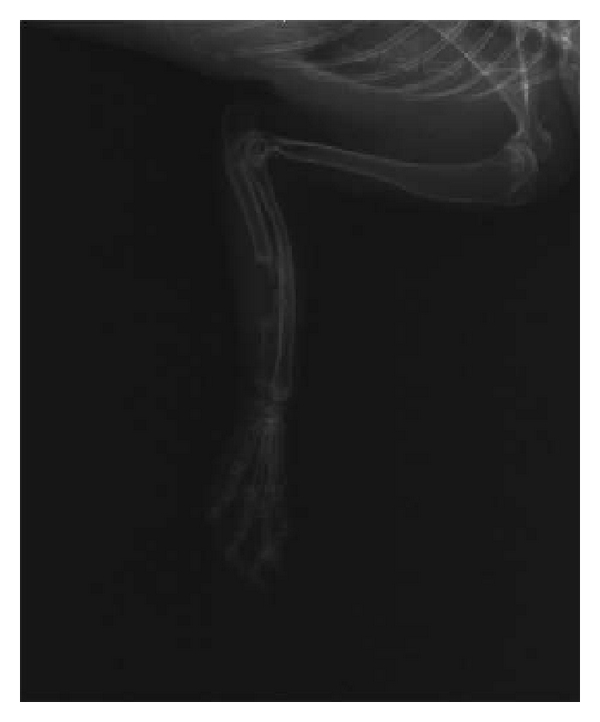

3.2. X-Ray Radiation Examination

X-ray radiation examination was conducted on right upper limb of 30 New Zealand rabbits immediately after surgery. Sufficient amount of scaffolds had been implanted into the bone defect site and the diameter of scaffold was bigger than ulna, indicating that it is a successful modeling for New Zealand rabbits bone defect. Small callus tissue and remaining scaffold can be observed in group A and group B 1 month after implantation; at the same time, periosteal proliferation was found in samples in group C. There was no statistically significant difference among three groups () according to chi-square test. At 2 months, plenty of calluses were expansively grown in group B; big callus volume was formed at the terminals of defect site in group A; no callus was formed in 8 samples of group C, and the difference among three groups was statistically significant () according to chi-square test. After 3 months, the volume of callus in group B was bigger than group A, and group C had marrow cavity sclerosis and bone atrophy which was typical bone nonunion performance. The difference among three groups was also significant (). The effective rate in group A was 14.29% (1 of 7 ulnas was healed), while the effective rate of group B was 33.33% (2 in 6). We excluded 2 dead rabbits in each group which was selected for histology HE staining test in the first 2 months. Figure 2 shows the example radiographs obtained at the 3rd month after surgery in three groups.

(a)

(b)

(c)